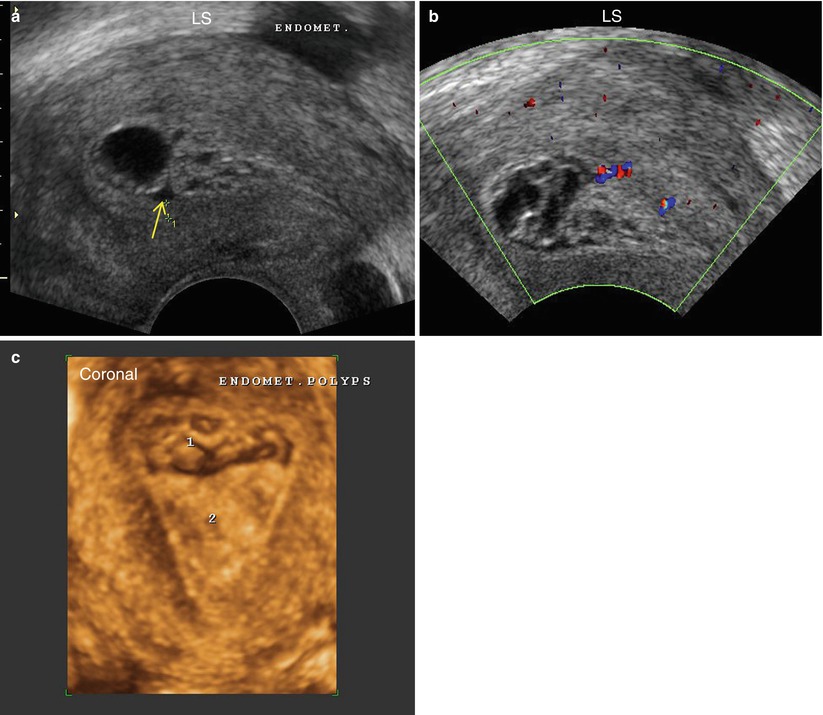

Awasome Echogenic Foci Endometrium Ideas. Web the best way to measure the endometrial thickness is on a midsagittal transvaginal image. Submucosal fibroid with degeneration adhesions:

Web a retrospective study was performed on 62 women, aged 28 to 81 years, who had echogenic foci of the endometrium and endocervix. Web hyperechoic myometrial foci are sonographic observation where the myometrium contains numerous bright echogenic foci. Web overview what is endometrial hyperplasia?

Web hyperechoic myometrial foci are sonographic observation where the myometrium contains numerous bright echogenic foci. Web a retrospective study was performed on 62 women, aged 28 to 81 years, who had echogenic foci of the endometrium and endocervix. The endometrium demonstrates a wide spectrum of normal and pathologic appearances throughout menarche as well as during the prepubertal and.

Web epidemiology they have an increased incidence with older age, postmenopausal state, atrophic endometrium, and endometrial polyps. Endometrial cancer is sometimes called uterine cancer. Immediately following menses, the endometrium is a thin.

Web the frequent presence of small echogenic foci within the inner myometrium in women who have had prior uterine instrumentation is reported. They can be detected during pelvic. They can be observed in very.

Submucosal fibroid with degeneration adhesions: Web the best way to measure the endometrial thickness is on a midsagittal transvaginal image. Web uterine polyps, also known as endometrial polyps, form as a result of cells in the lining of the uterus (endometrium) overgrowing.